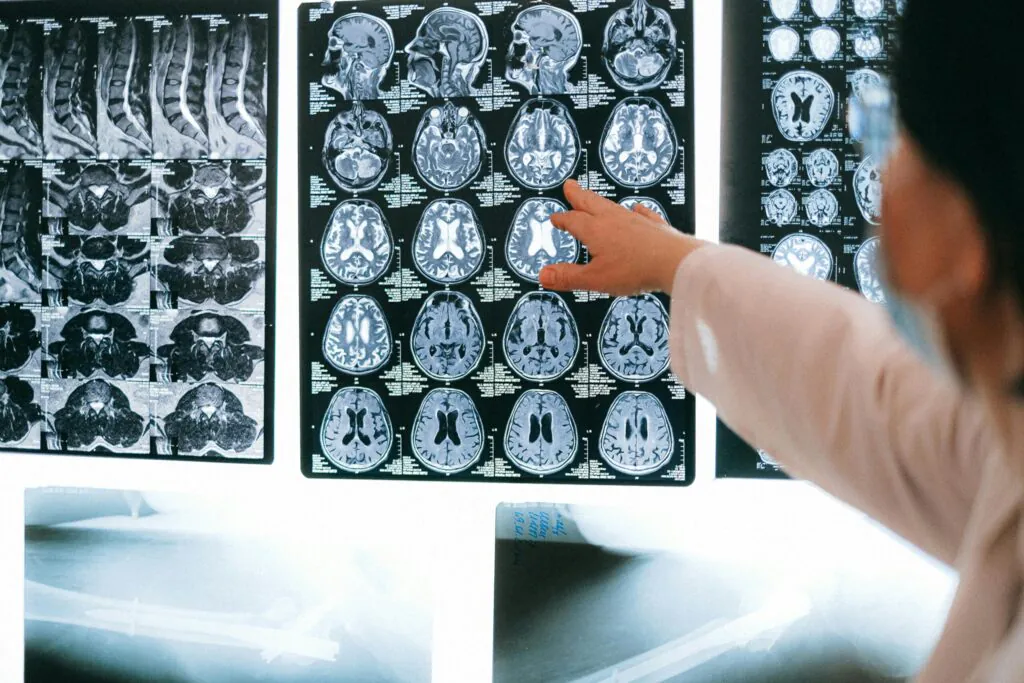

Medical Travel is the rapidly-growing practice of travelling across international borders to seek best healthcare services.

Patients travel abroad for medical care because of affordability and better access to a higher or more specialized quality of care.